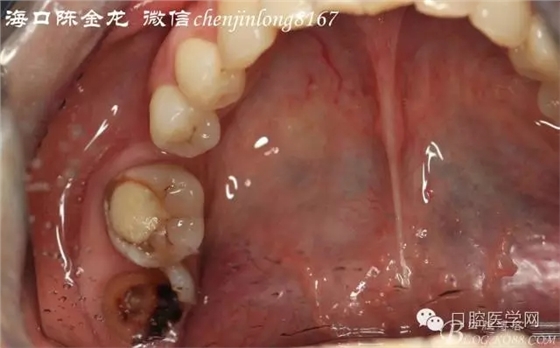

咬合無干擾

后期主要注意三個(gè)方面:

第一牙髓情況

第二牙周膜連續(xù)情況

第三根尖吸收情況

種植成功后觀察是否需要根管治療,后期通過正畸方法關(guān)閉右下6的拔牙間隙。